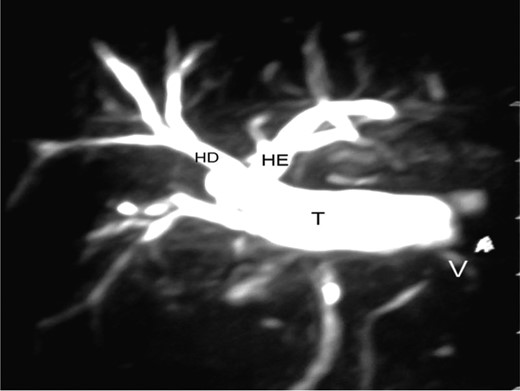

Magnetic resonance cholangiography performed 45 months after surgery showed a functioning tube (Fig. 8). The patient continues to be anicteric and laboratory tests are normal.

Right hepatic duct (RH), left hepatic duct (LH), interposed jejunal tube (T) and antireflux valve (V).